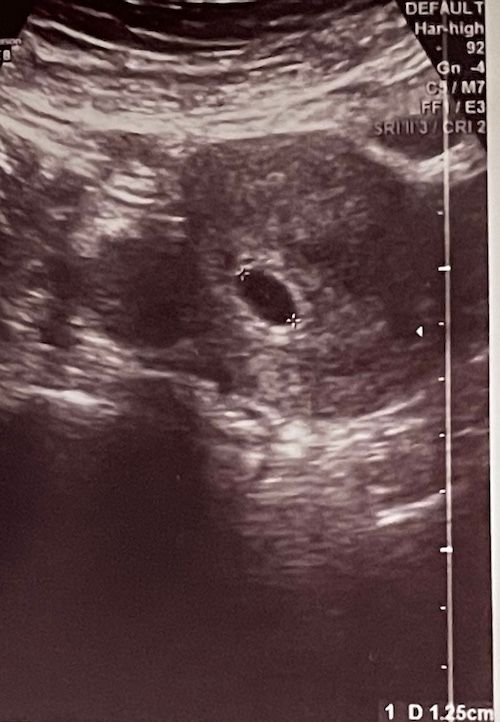

Анэмбриония? Узи 6+4

Девочки, по месячным 6+4, узист не нашла эмбриона, только пя 12,5 мм. Неужели пустое??

Алина Саидова, у вас четко виден желточный мешок. А у автора пустое пя.

Там что-то видно и похоже даже прикрепление, но слишком тёмная картинка. Мне кажется, со сроком перепутали, может он меньше на неделю и аппарат плохой.

И насколько мне известно пя считают с внешнего контура, а не внутренний. У вас размер больше, чем 12,5

Узист не нашла,а я вижу даже не переглядываясь😉

ПЯ маленькое для такого срока. Возможно, срок меньше, вот и эмбриончика не видно.